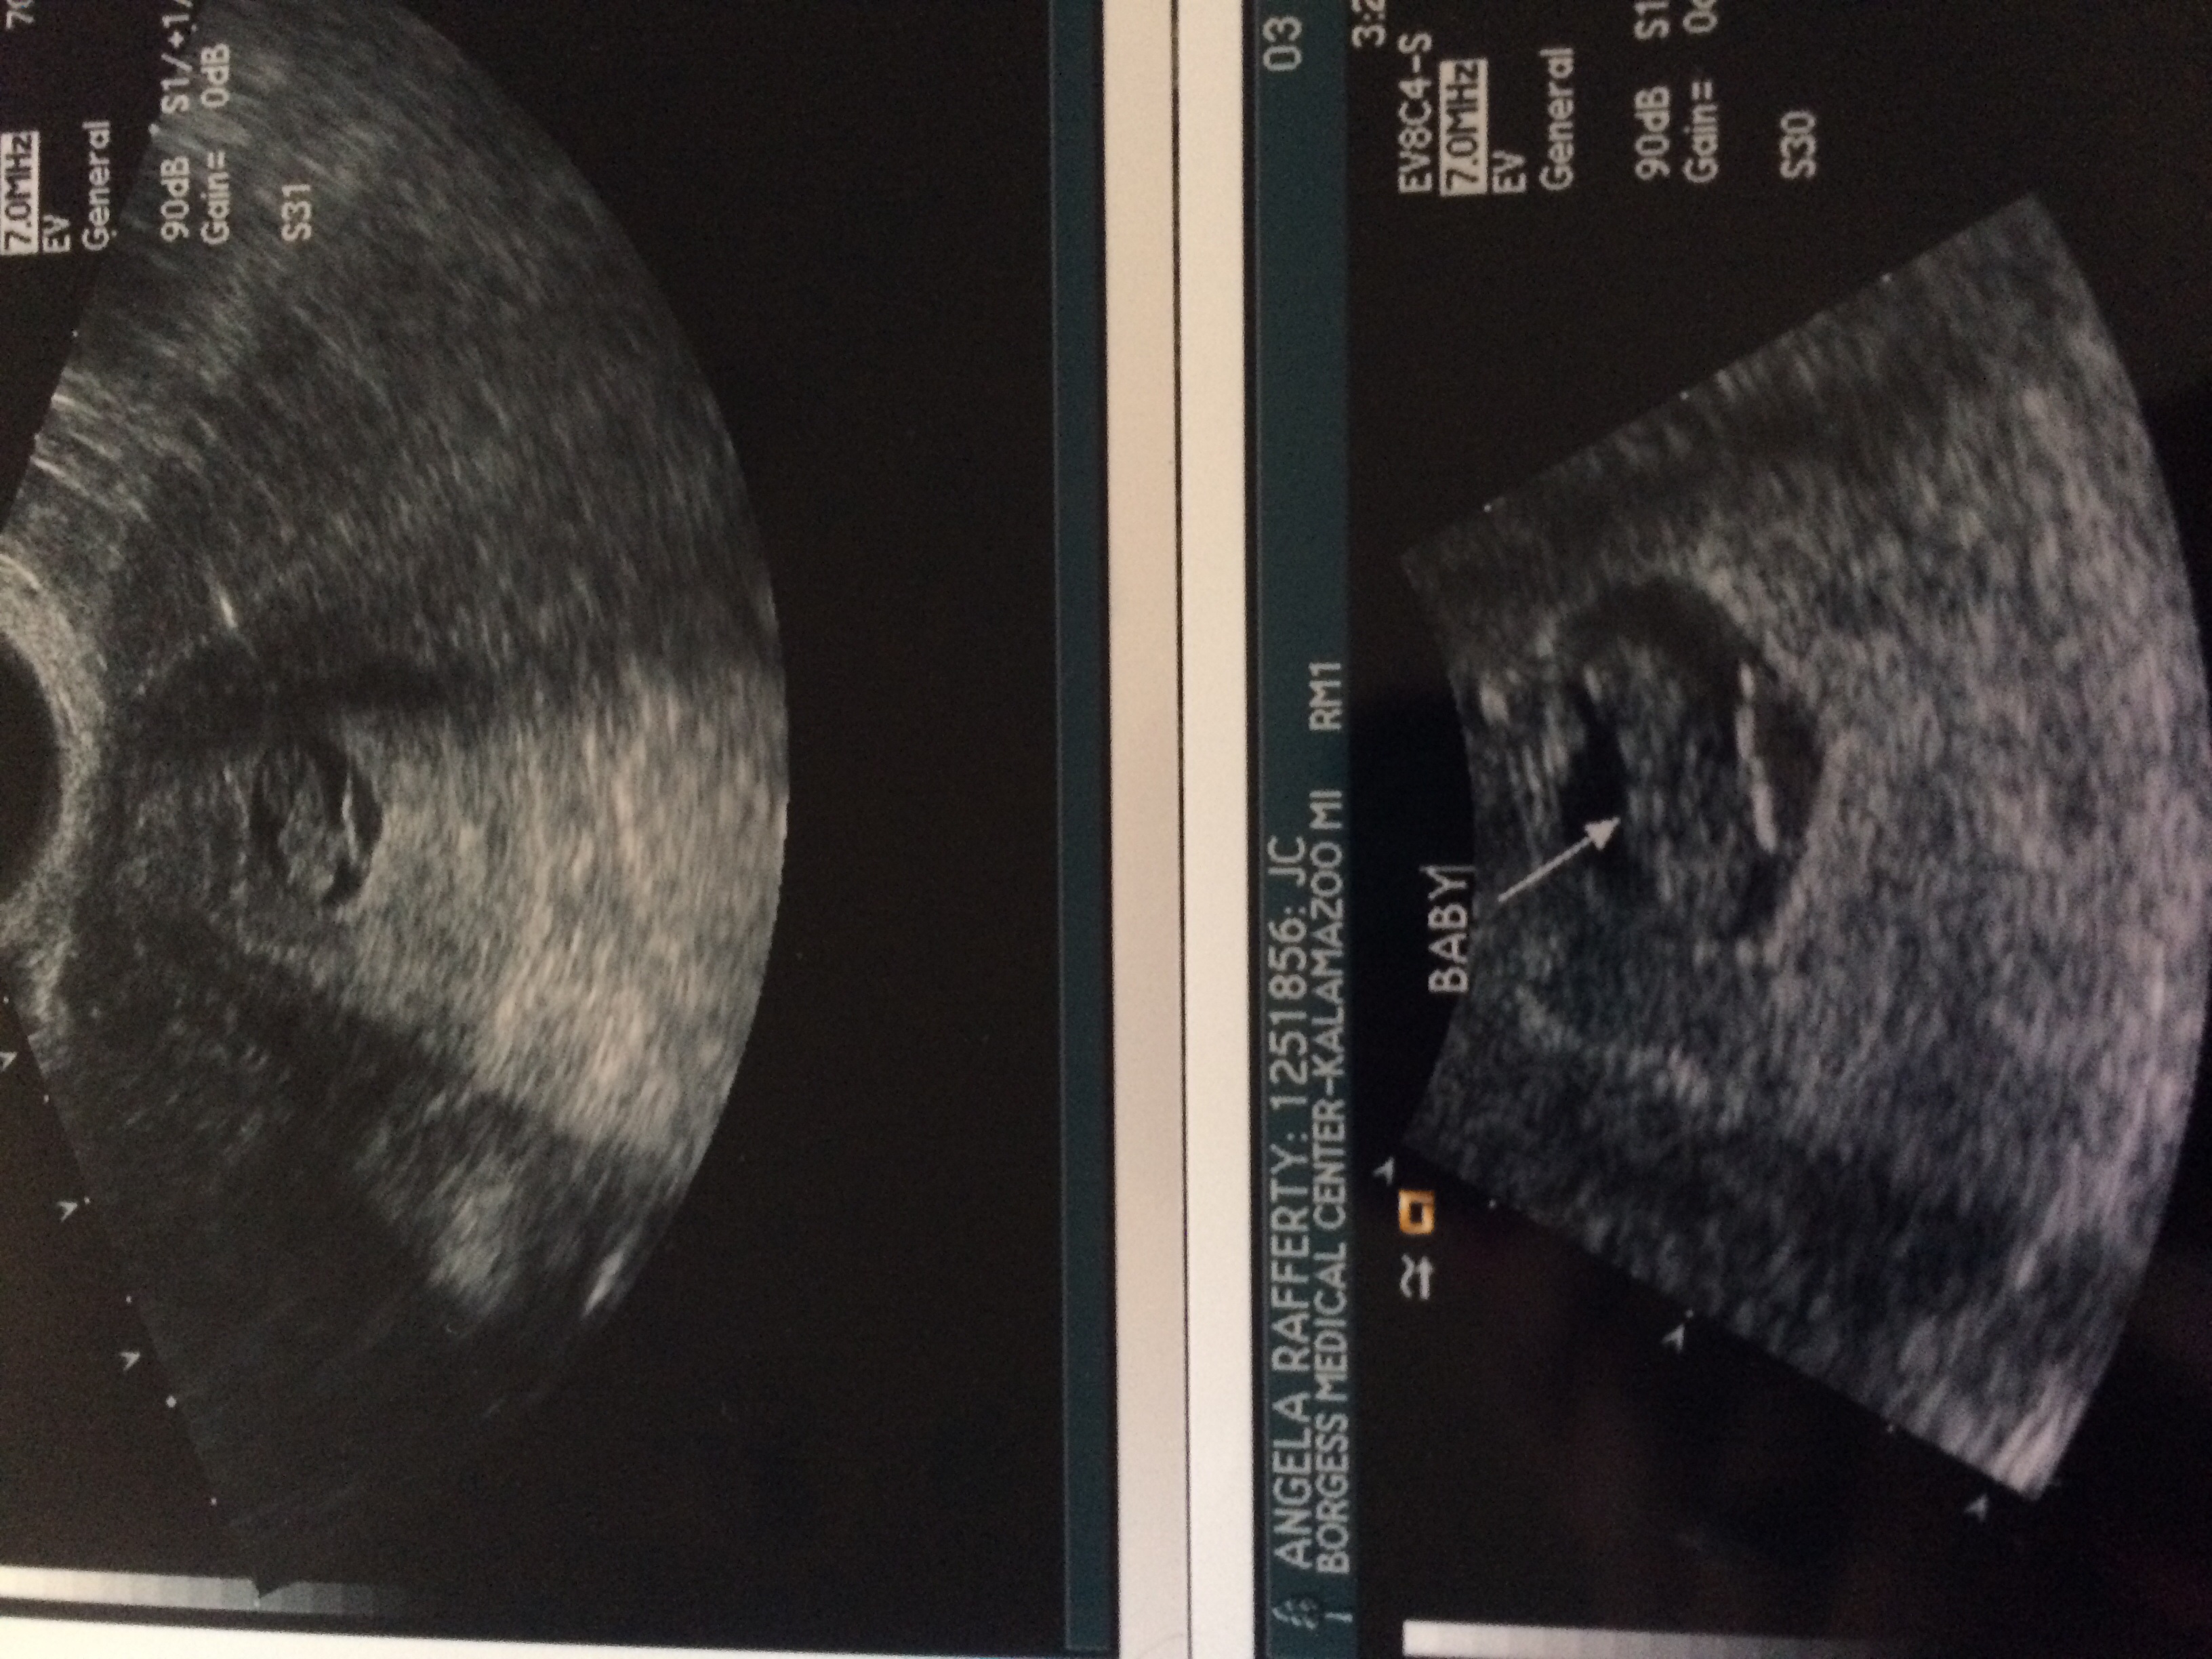

Okay, I was first having problems 2 weeks ago. Right around 5 and a half weeks. My hcg was not going in up in fact it was going down by a couple houndred every day. My progesterone was 3 so they put me on prometrium BID. I have had weekly ultrasounds and baby is growing and still has a heartbeat. My hcg has been going up over the last week, but not doubleing. At my last ultrasound they said my gestational sac was measuring 5w4d but baby was measuring 7w6d. That is about a 3mm difference between baby and edge of sac. I have been researching it and found that it will most likely result in miscarriage, but we wondering if there is anything I can do?!?! I mean they have been saying miscarriage for 2weeks. I want this baby more than anything. But I'm so sick of being in limbo. Please, anyone with similar situations or advice or even support help me out.